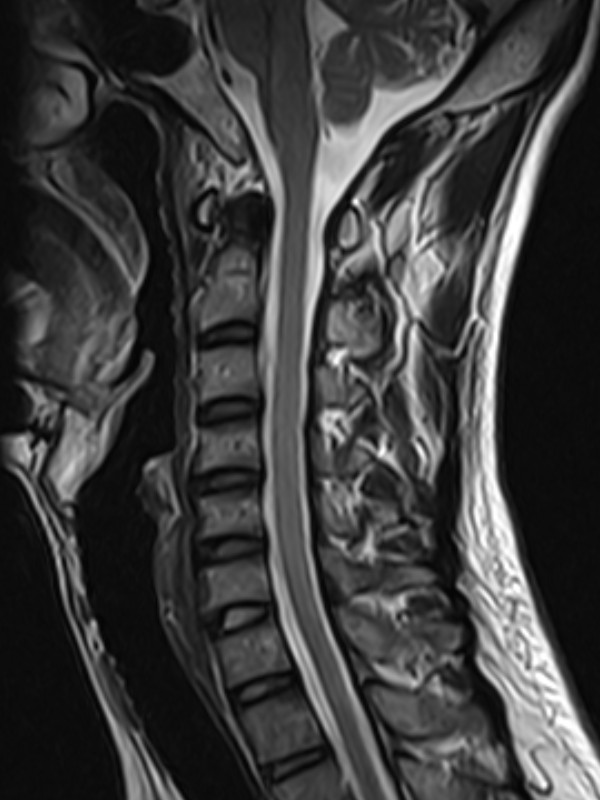

颈椎-STIR